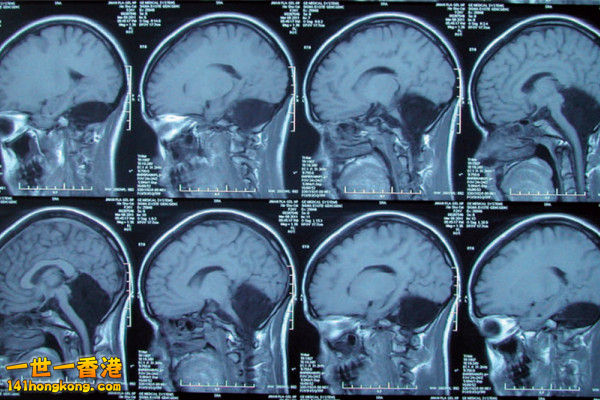

大陸 24歲女暈眩求診 竟發現沒有小腦

中國大陸 山東一名24歲女子因爲嚴重暈眩和噁心,到醫院求診,

結果檢查發現該女子居然沒有小腦 / Cerebellar !

根據《New Scientist》報導,女子就醫後,向醫生表示,她常常沒辦法平穩走路,

母親也說,她直到7歲才會走路,6歲時不太會講話,而之前則口齒不清。

小腦的位置在頭骨的後方,主要控管平衡,以及運動、說話能力,所佔腦部的總體積10%,

但卻含有近一半的神經元。

一般小腦若出問題,可能導緻精神障礙、運動障礙,甚至造成癲癇。

然而,這名女子天生有腦洞,卻僅有輕度的語言問題,發音稍微含糊。

醫生表示,雖然這種病例並非首次發生,但通常這類病患無法活太久,甚至到死亡後

才會發現問題所在,這名女子天生就沒有小腦,如今卻活到24歲,

且隻有輕微的語言障礙,難以解釋的狀況引發醫界高度關注,

目前推測可能是大腦皮質取代了小腦功能。